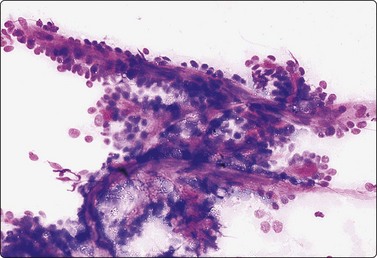

image image

Fig. 4.25 Chronic sialadenitis

Fragments of epithelium mainly of ductal origin showing mild reactive atypia and some squamous metaplasia; fragments of fibrous stroma; relatively few chronic inflammatory cells. (A, MGG, IP; (B, Pap, IP).

Criteria for diagnosis

Purulent aspirate in acute, infective sialadenitis,

Scanty material of mainly ductal epithelial cells, few acinar cells in chronic sialadenitis,

Sheets of ductal epithelium showing regenerative atypia and/or squamous metaplasia,

Variable numbers of inflammatory cells, usually few in chronic sialadenitis,

Fragments of fibrous stroma.

Most cases of chronic sialadenitis referred for FNB are in a late stage when interstitial fibrosis and atrophy of acinar tissue have taken place. The inflammatory cell infiltration may have subsided and may be sparse and patchy. FNB smears are therefore often scanty, mainly of ductal epithelial cells associated with only few acinar cells and inconspicuous inflammatory cells. Fragments of fibrous stroma are often present (Fig. 4.25). Crystalloids may be present in the aspirate.95 Regenerating ductal epithelium in chronic sialadenitis may undergo squamous metaplasia and may appear atypical (Fig. 4.26). Mucus-like material from dilated ducts may be present. This may be suggestive of a neoplastic lesion or even of malignancy, mainly low-grade mucoepidermoid tumor. Multiple sampling and clinical correlation usually solves the problem.